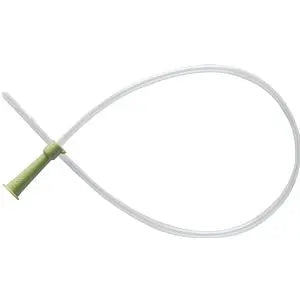

10fr Adoles. Easy-Cath 50 - Box Of 50

12fr Catheter -Easy-Cath - Box Of 50

12fr Catheter Easy-Cath 5 - Box Of 50

14fr Catheter Easy-Cath 5 - Box Of 50

14fr Female Easy-Cath - 5 - Box Of 50

14fr Soft Easy Cath" 50 - Box Of 50

16fr Catheter Easy-Cath 5 - Box Of 50

16fr Catheter Easy-Cath 5 - Box Of 50

6fr Pediatric Easy-Cath 5 - Box Of 50

8fr Pediatric Easy-Cath 5 - Box Of 50